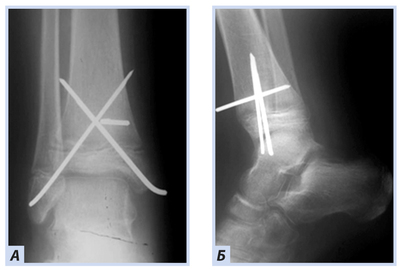

Когда мне было 11 лет, бабушка слегла. Перелом тазовой кости, который нормально не смог срастись (спасибо нашим врачам, козлы). Мать продолжала заботиться о бабушке, да и я не отлынивал – всё-таки бабуля. Но, мать видимо утомило, жить одной. Поэтому в 14 лет в моей жизни появился отчим (назовём Виталий), я его звал по имени, на что он дико обижался. Он почему-то ждал, что я его папой называть буду.